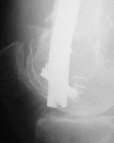

I presented a series of ~25 such cases at EuroTrauma'2004. Many cases were discussed here. I attach am example. Look also recent cases at http://www.hwbf.org/hwb/conf/alex58/scfx.htm,

http://www.hwbf.org/hwb/conf/alex63/alex63.htm

THX, initial images are

1,

2.

At that moment we had in stock only the 10 mm solid nails so of course there was no idea about early weight bearing. But it was quite enough for early knee ROM excersises (see attached). Two locking screws through the distal block provided that.